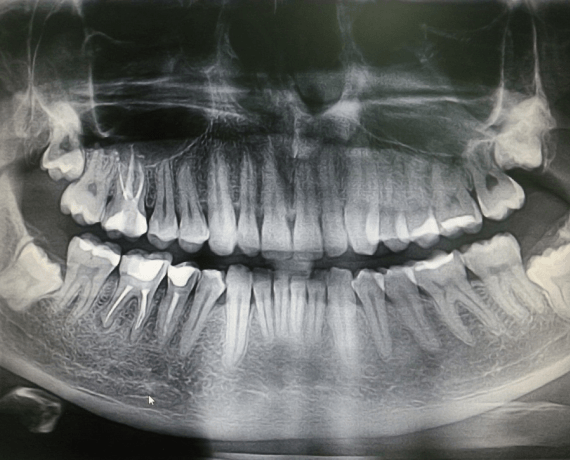

Стоматологические Исследования: Рентген Инвагинации Зубов